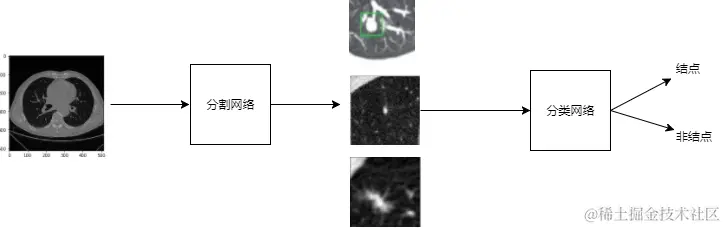

本次竞赛要求从数千例CT 影像中找出肺结节的位置,并给出概率。相比于图片,CT影像可以看成3维的数据,更大更耗费资源,也更难以提取特征。我们采用分割+分类的方法,先利用分割网络从CT影像中找出疑似的结节,再利用分类,对找出的疑似结节进行判断。 我们采用了基于3D的解决方案,因此能提取更多的空间信息。同时我们在设计网络的时候,充分考虑不同结节的尺度,识别的难易程度,结合Residual和Inception的结构思想,设计了ReCeption结构,在不同尺度,分辨率的结节上都有着较好的效果。团队队员第一次参加竞赛,经验不够丰富,基本未使用模型融合的方式,主要是简单的boost方法。

此次比赛,我们的方案是分割+分类的方法,分割部分使用UNET,找出疑似节点,而分类部分使用类似ResNet结构神经网络,对找出的疑似节点给一个概率。最后初赛数据集得分最高的froc为0.750,复赛数据集得分最高的为0.600。

我们的算法分为3步:

1. 基于3D CNN+Unet/Inception/Resnet的分割网络,用以找出疑似结点。利用结节标注信息生成的结节mask图像,训练基于卷积神经网络的肺结节分割器。

2. 基于ResNet的分类网络,判断每一个疑似结点是否是真阳性。 找到疑似肺结节后,可以使用图像分类算法对疑似肺结节进行分类,得出疑似肺结节是否为真正肺结节的概率

3.利用类似adaboost的方法训练多个一样的分类模型,不断的提升分类的准确率。

liucheng.png